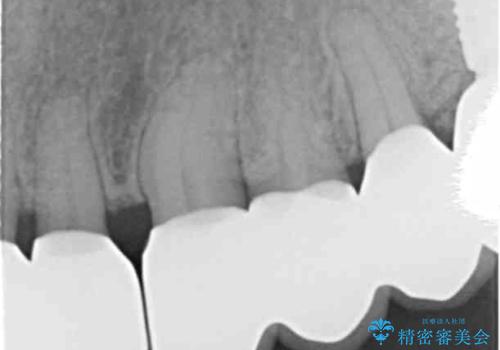

- 夜間のくいしばり、はぎしりが激しく全体的な歯周病が進行し、治療を希望され来院されました。

歯周ポケットの徹底的な除去を行なったのち、歯の揺れを抑え、過大な力がかからぬよう連結クラウン(歯周補綴)を行い強大な力に対抗します。

夜間の歯ぎしりにはナイトガードを用いて大きな力がかからないような対処が必要です。